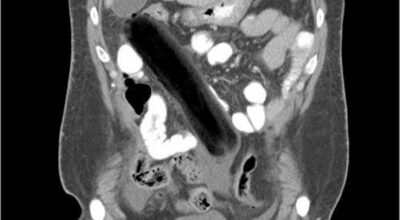

Esta recopilación de imágenes recoge alguna de las situaciones más estrambóticas que se han podido dar en una sala de rayos X. Todas ellas tienen algo en común: Son objetos extraños para el cuerpo humano que, de alguna manera han encontrado una vía de entrada, pero se han perdido a la hora de encontrar la de salida.

Muñecas de juguete descabezadas, botellas, armas, frascos, botes de plástico, teléfonos y hasta una cinta de casete pueden encontrarse en esa suerte de “punto limpio” al que ha quedado reducido el interior de los afectados.